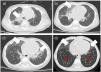

Los datos descritos en nuestros 6 pacientes demuestran que la NEHI es una de las enfermedades intersticiales pulmonares de la infancia de mejor pronóstico. El retraso en el diagnóstico puede estar relacionado con la inespecificidad de los síntomas respiratorios iniciales y la baja sospecha clínica dada la rareza de la entidad3, basándose este en la clínica respiratoria descrita en el score-NEHI de inicio entre los 1-12 meses de vida (generalmente en <6 meses) y en las típicas imágenes de la TC pulmonar de vidrio deslustrado en língula y/o lóbulo medio y atrapamiento aéreo con inversión del cociente ventilatorio normal5 (fig. 1). Aunque se sugiere un posible origen genético, no se ha podido identificar con exactitud el gen causante y a ninguno de nuestros pacientes se realizó este estudio. La biopsia pulmonar se reserva para los casos en los que la evolución no sea la esperada6.